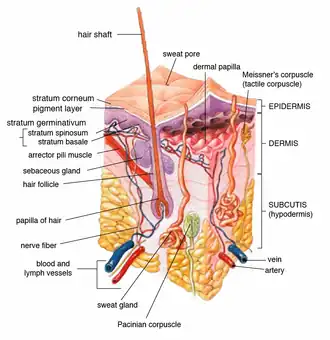

Cross-section of all skin layers. A hair follicle with associated structures. (Sebaceous glands labeled at center left.) | |

Sebaceous glands are found in hair-covered areas, where they are connected to hair follicles. One or more glands may surround each hair follicle, and the glands themselves are surrounded by arrector pili muscles, forming a pilosebaceous unit. The glands have an acinar structure (like a many-lobed berry), in which multiple glands branch off a central duct. The glands deposit sebum on the hairs and bring it to the skin surface along the hair shaft. The structure, consisting of hair, hair follicles, arrector pili muscles, and sebaceous glands, is an epidermal invagination known as a pilosebaceous unit.[4]

Sebaceous glands secrete the oily, waxy substance called sebum (Latin for 'fat, tallow') that is made of triglycerides, wax esters, squalene, and metabolites of fat-producing cells. Sebum lubricates the skin and hair of mammals.[9] Sebaceous secretions in conjunction with apocrine glands also play an important thermoregulatory role. In hot conditions, the secretions emulsify the sweat produced by the eccrine sweat glands and this produces a sheet of sweat that is not readily lost in drops of sweat. This is of importance in delaying dehydration. In colder conditions, the nature of sebum becomes more lipid, and in coating the hair and skin, rain is effectively repelled.[10][11]